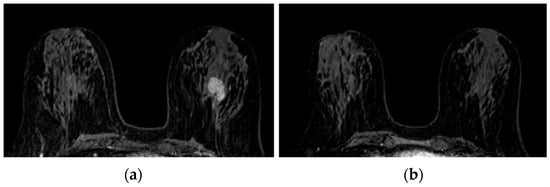

The response to NAC was not associated with FGT, BPE baseline, as well as BPE in the middle and final step (Table 8). We counted the cases that found BPE reduction to be at least one BIRADS class at the middle and/or final step MRI compared to the baseline. The response to therapy was found to be significantly associated with BPE reduction (Figure 4). Indeed, 61.2% and 18.4% of patients who showed a reduction in BPE after the first three months of NAC had a partial and a complete response; only 45.2% of patients who did not show a reduction in BPE after the first three months of NAC had a partial response, while 29.0% with the disease remained stable (Table 8). Therefore, sensitivity and specificity for BPE reduction predicted a partial or complete response was 77.6% and 45.2%, respectively, with positive and negative predictive values of 55 and 24, respectively. In addition, there was no significant association between a response to therapy or dosing regimen (Table 9).

Figure 5, Figure 6 and Figure 7 show three different examples of responses to cancer therapies according to the RECIST criteria.

Figure 5. Complete pathological response (pCR): 2,5 cm deep retroareolar tumor on the left breast in the pre-treatment baseline survey ((a) triple negative) no longer visible at the end of the therapy cycles (b). Reduction of a BPE class (moderate to mild) is observed.